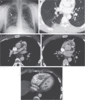

Imaging Studies of the Chest.

A posteroanterior chest radiograph (Panel A) shows a masslike opacity in the midlung zone behind the right hilum (arrow) and enlarged pulmonary arteries.

Axial contrast-enhanced CT angiographic images were obtained at the lung-window setting (Panel B) and at the mediastinal-window setting (Panels C and D) at the level of the midchest.

A mottled, wedge-shaped air-space opacity is present in the periphery of the right lower lobe (Panel B).

A smooth, large, central filling defect (Panels B and C, arrows) is present that extends from the main pulmonary artery (MPA) to the right pulmonary artery (RPA).

Central filling defects are also present in the interlobar and lobar branches of the right pulmonary artery (Panel D, arrows); the right ventricular outflow tract (RVOT) contains an irregular central filling defect with central contrast-filling channels rather than enhancement.

An axial CT angiographic image (Panel E) shows a dilated right ventricle (RV), with a ratio of RV diameter to left ventricular (LV) diameter of 1.6 (normal, <1); a heterogeneously enhancing filling defect is evident in the RV cavity (arrow), as well as in the right atrium (not shown).